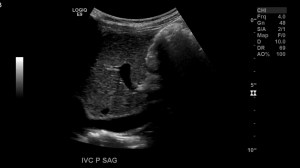

image6